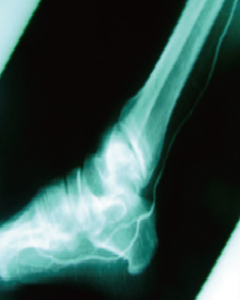

버거씨병

Buerger’s Disease-

Before

-

줄기세포 치료 30일 후

줄기세포 치료 120일 후

- 하지 혈류 개선

- 치료 후 종아리 근육부위에 새로운 혈관이 형성되었고 혈류의 흐름이 호전되었습니다.

- 족부 혈류 개선

- 치료 후 종아리 족부에 새로운 혈관이 형성되었고 혈류의 흐름이 호전되었습니다.